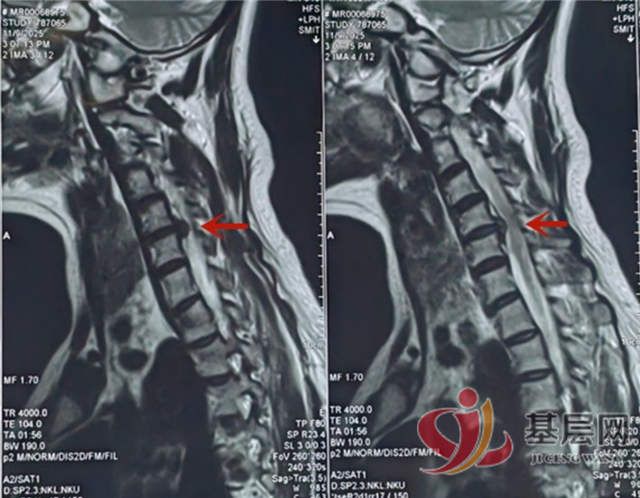

患者颈5/6椎间盘突出